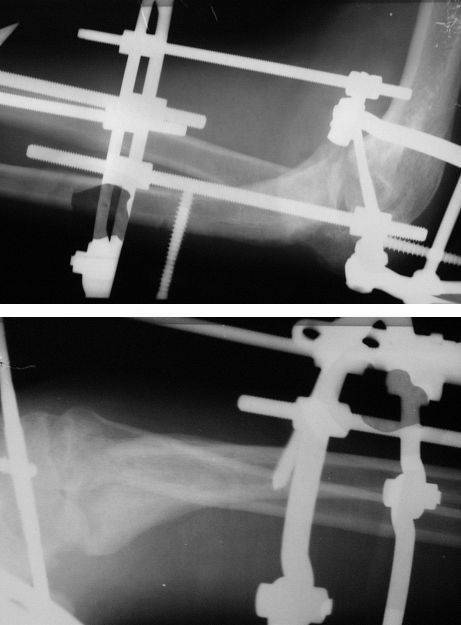

Коллеги! Сделан первый этап операции - синтез спице-стержневым аппаратом. При умеренной дистракции локтевого сустава (0,5 мм в сутки) производится дорзальная тракция дистального отломка локтевой кости (1 мм в сутки) стержнем Штеймана при стабилизации olecranon отдельным стержнем. Стержень в olecranon ввелся очень легко - остеопороз. Р-граммы через 4 дня после операции.

Николай

Николай, Вы довольно сильно рискуете, вводя стержень в такой маленький и порозный отросток. нагрузка будет возрастать по мере компрессии. Не факт, что в таком сроке после травмы удастся компрессия отломков, а вот перфорация отростка и (или) его раскол очень может приключится.

Как вариант вводить две параллельные спицы (можно с упорами навстречу) хорошо их натягивать (!) в полукольце. Это вплне безопасно по прорезыванию и отросток управляемый.